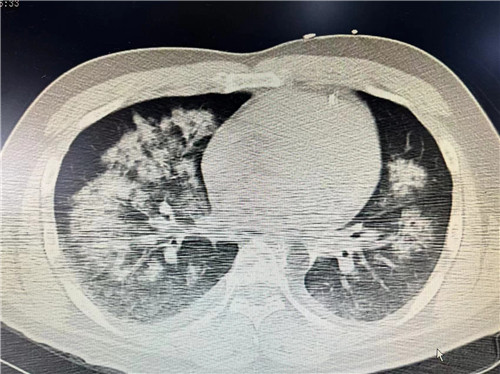

CT结果提示严重肺水肿

到达捷克论坛 时,距离小王发病已经过去8小时,人已经处于休克昏迷状态,急诊检查确诊左主干急性闭塞,也就是心脏主要供血的通路中断了,需要立即手术,而病情的延误使小王出现了休克并严重的肺水肿,术中随时可能出现心跳骤停,死亡风险极高。